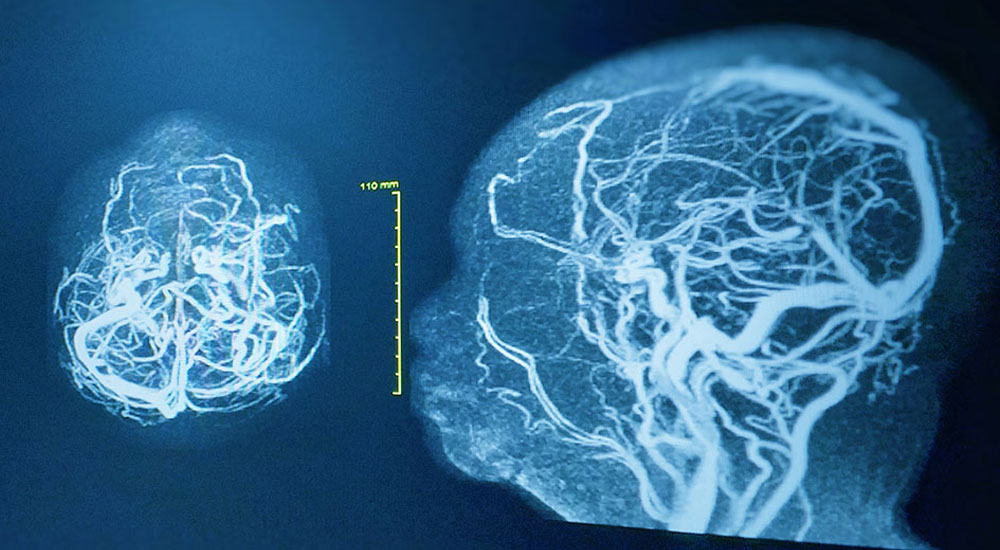

Cerebral angiography is a diagnostic test that uses an X-ray. It produces a cerebral angiogram, or an image that can help your doctor find blockages or other abnormalities in the blood vessels of your head and neck. Blockages or abnormalities can lead to a stroke or bleeding in the brain.

For this test, a doctor injects a contrast medium into your blood. The contrast material helps the X-ray create a clear picture of your blood vessels so that your doctor can identify any blockages or abnormalities.